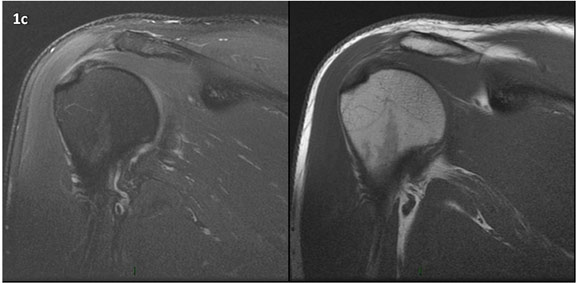

Figura 1 (a-g): Imagens consecutivas de RM no plano coronal nas ponderações DP com supressão de gordura (DP SG) à esquerda e T1 à direita. Clique na seta para passar as imagens.

Figura 1a’ mostrando rotura parcial articular na inserção do supraespinhal (setas azuis).

Figuras 1b’ a 1g’ mostrando atrofia da porção superior do músculo redondo menor (seta salmão), com lipossubstituição mais evidente das mais fibras laterais (seta amarela). As fibras mais inferiores e mediais têm atrofia menos evidente.

Repare que estas alterações não são evidentes nas imagens com supressão de gordura.